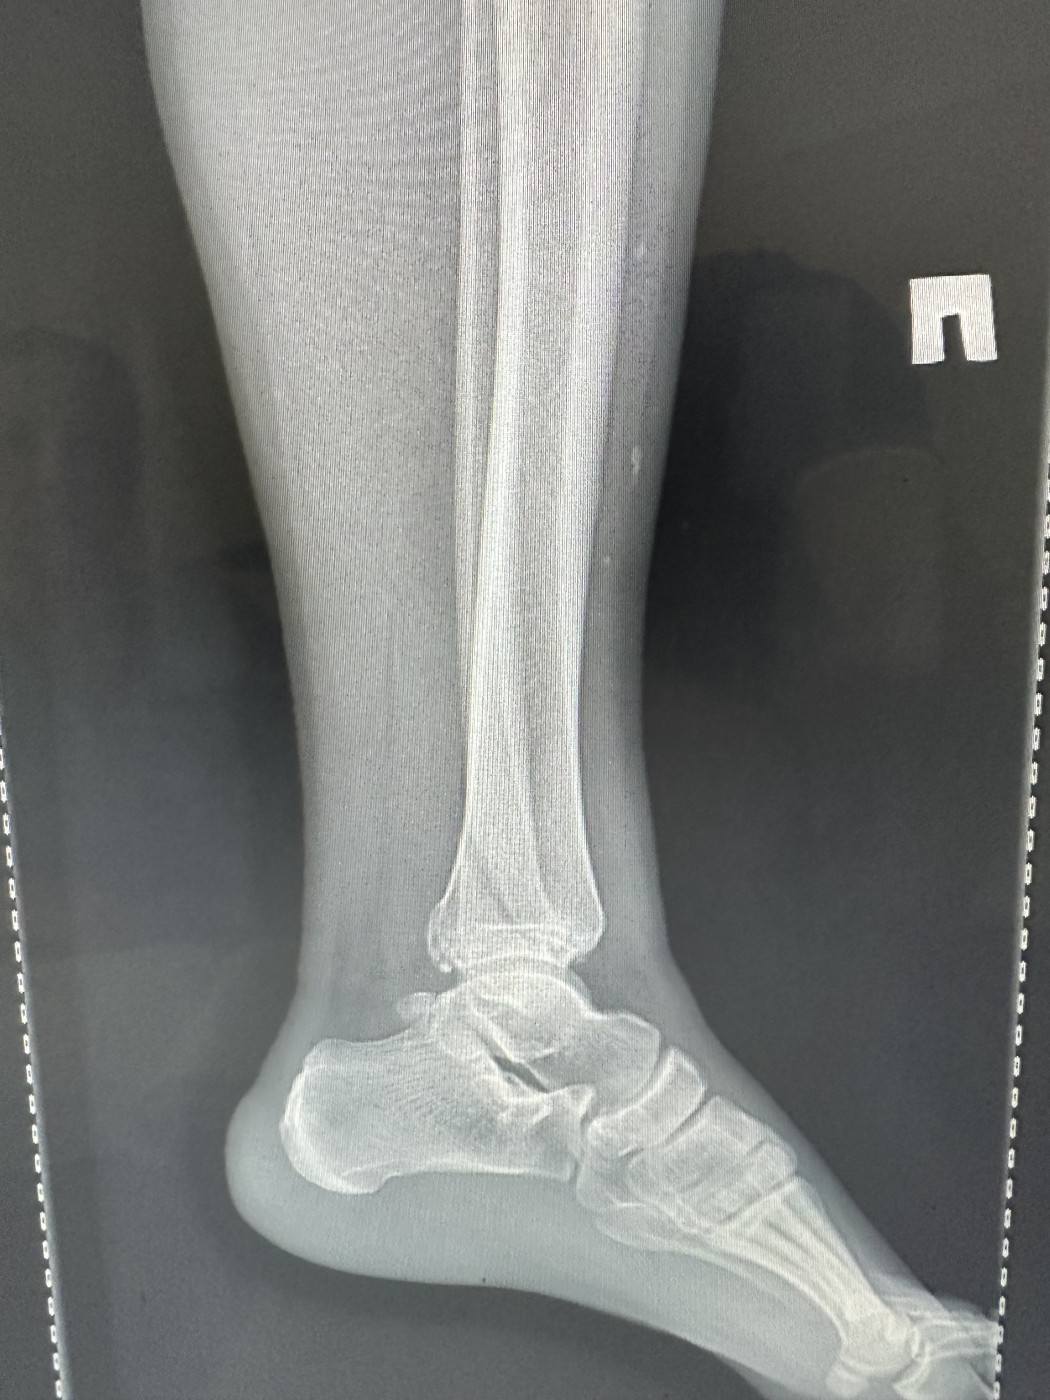

Есть ли перелом?   1 ответ

Местные врачи говорят сложнейший перелом и нужно делать какую-то операцию,хотя нога даже не болит. Пол мужской 29лет

5 июн 2025 10:05